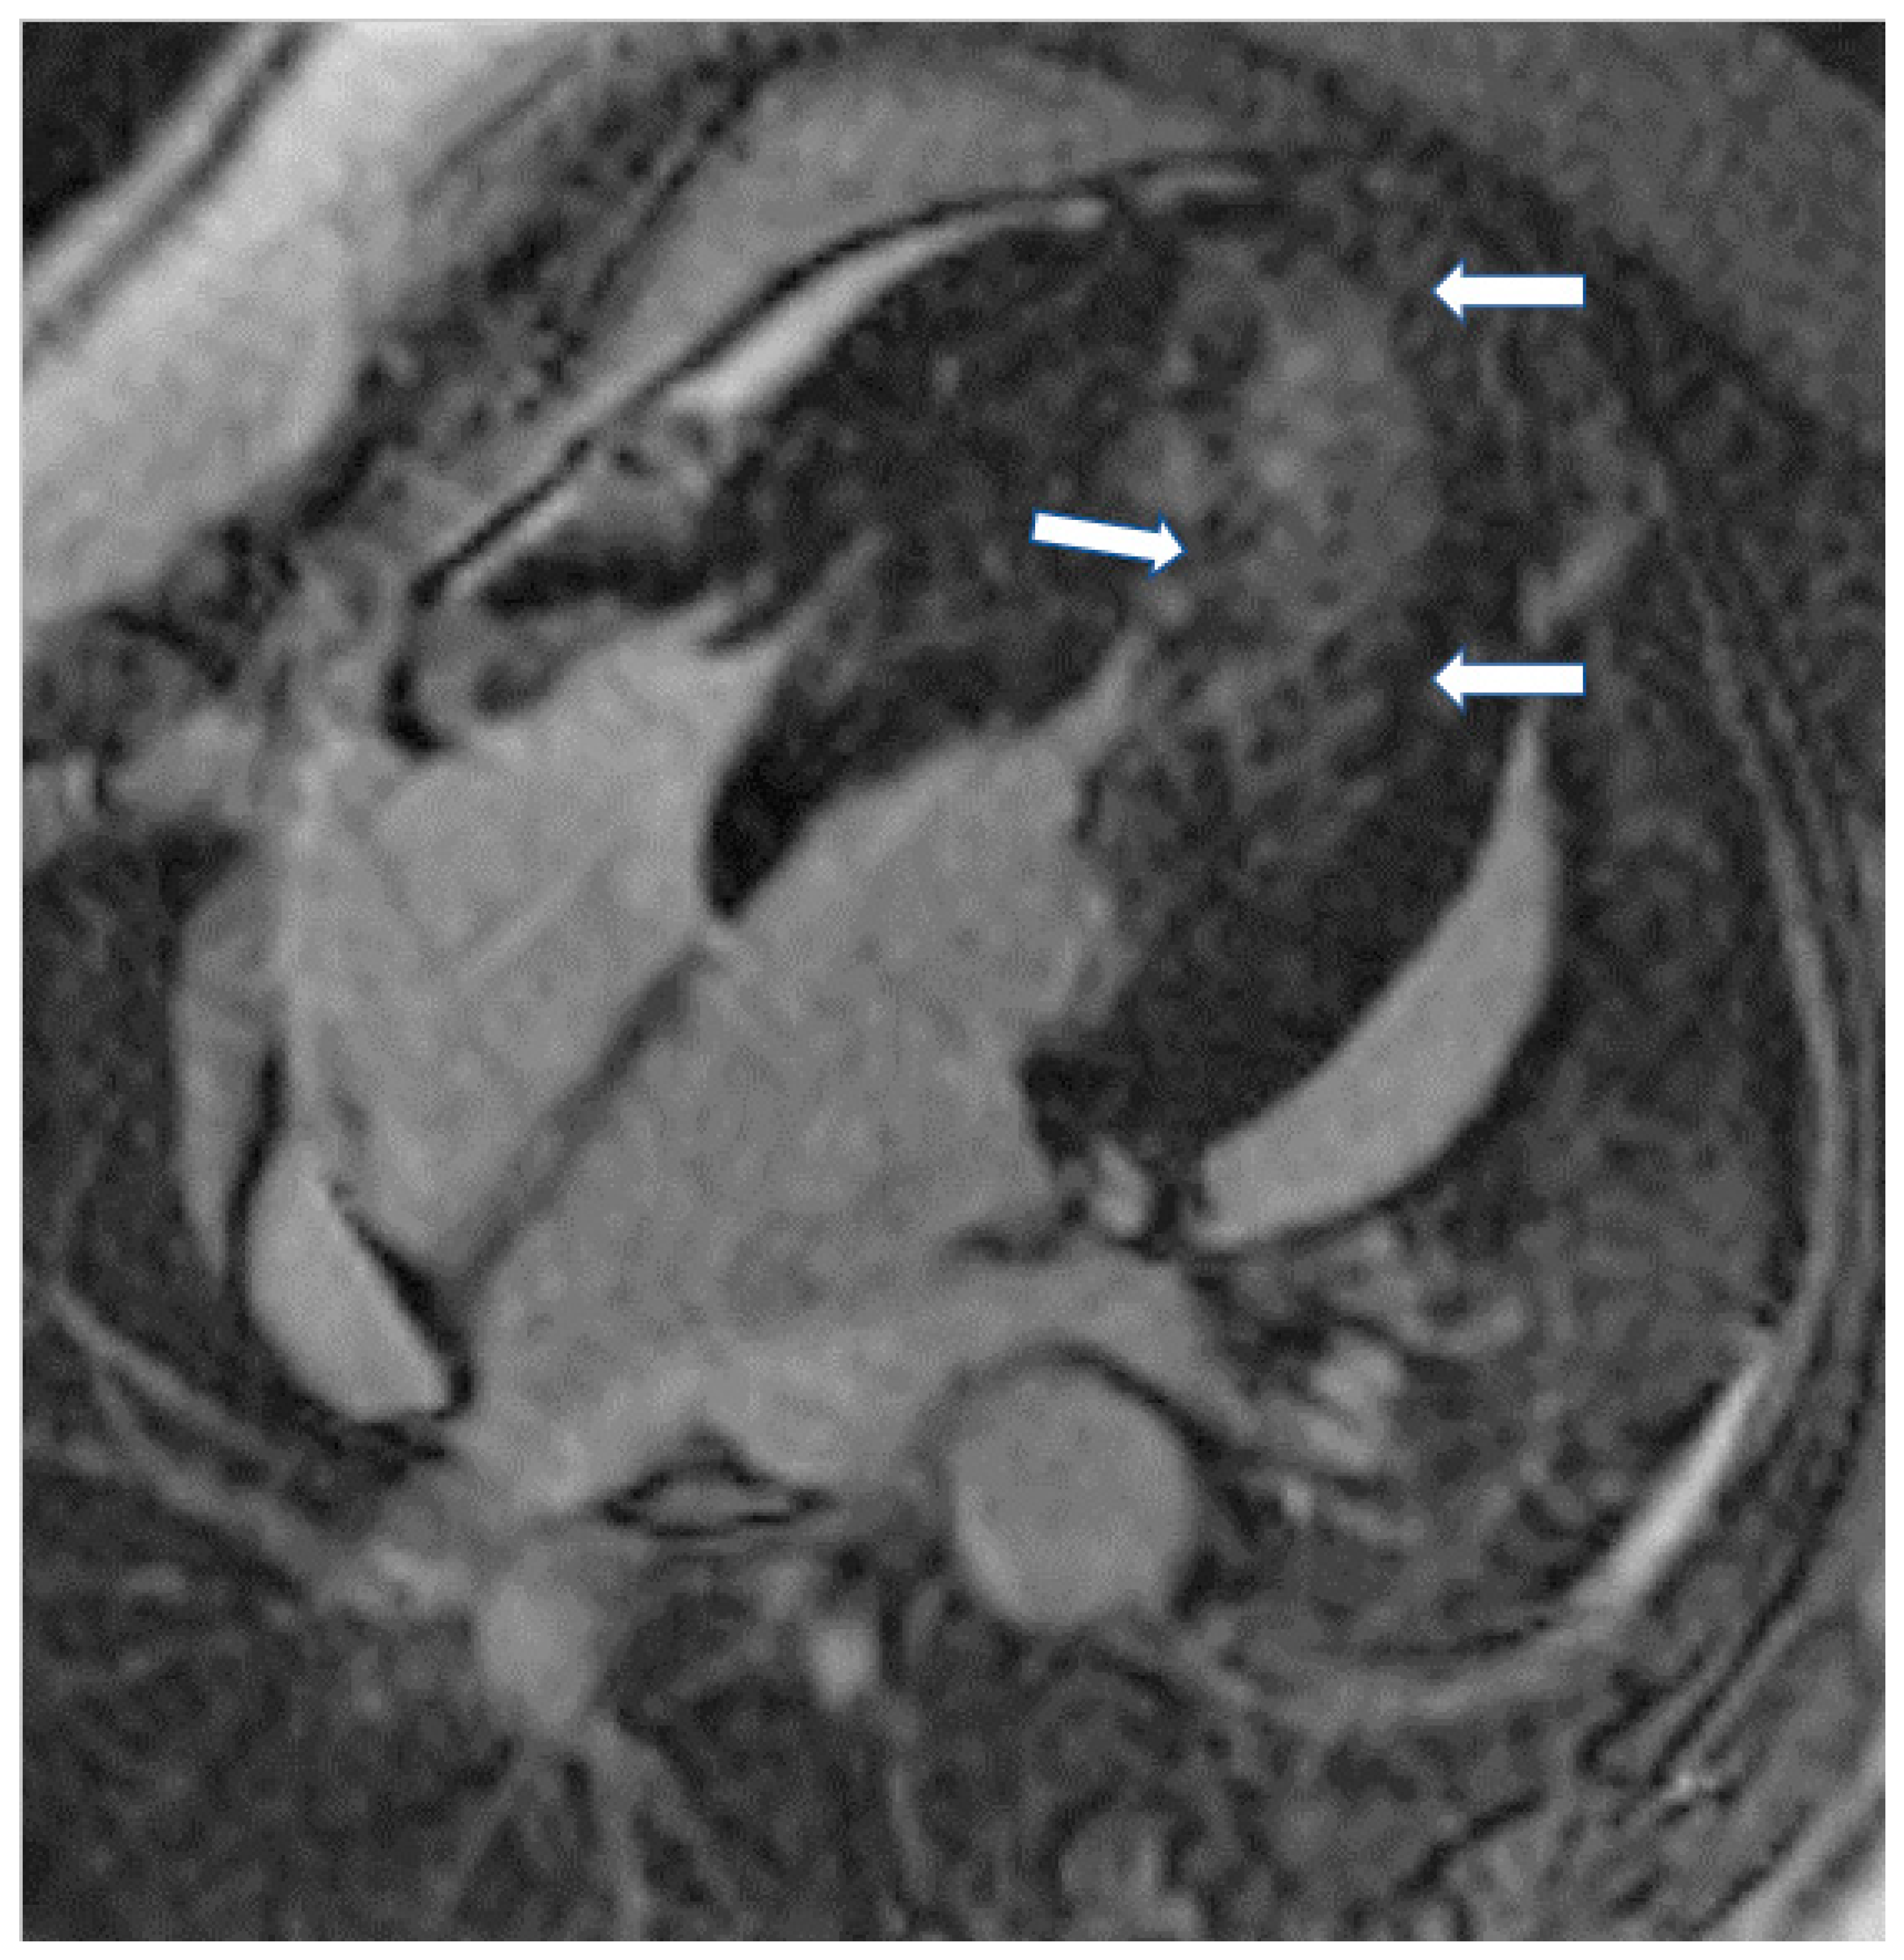

Finally, cardiac amyloidosis (CA) (Figure 5A,B), Takotsubo cardiomyopathy (TCM), non-compaction cardiomyopathy (LVNC), and cardiomyopathies associated with neuromuscular, metabolic, and autoimmune diseases are included in the unclassified cardiomyopathies.

Figure 5.

(A) Short axis LGE image showing diffuse amyloidosis (arrows). (B) Matching native T1 mapping of the same patient.

In CA, CMR shows diffuse hypertrophy of both LV-RV, in contrast to HCM, which is usually associated with focal hypertrophy. Thickening of the interatrial septum and posterior right atrial wall >6 mm is also common in CA [77]. LGE is the hallmark of cardiac amyloidosis on CMR. In a study by Vogelsberg et al. [78], LGE was found in 79% of patients with CA. LGE may involve the entire subendocardium, extending into the neighboring myocardium. Ejection fractions, LV end-diastolic volume and myocardial mass were not significantly different between the CA group and the other groups with various cardiac disorders. In this study, the average interventricular septum was 17 ± 4 mm in the CA group compared with 13 ± 3 mm in the non-CA group [78]. A more recent study by Syed et al. [79] showed that CMR demonstrated LGE in 97% of patients and increased LV wall thickness in 91%. We should also note that LV amyloid accumulations occur according to the following steps: (a) no evidence of LGE, (b) appearance of subendocardial LGE (typical pattern), and (c) progression to transmural LGE [80].